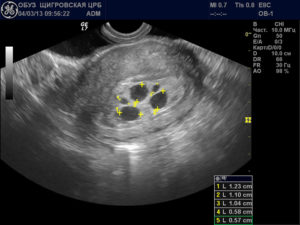

Решающее значение в диагностике анэмбрионии принадлежит дополнительным методам. И основную роль в этом играет ультразвуковое исследование матки. По его результатам определяют следующие признаки патологии:

Согласно данных УЗИ, выделяют два типа анэмбрионии. Первый характеризуется тем, что диаметр плодного яйца не превышает 25 мм, размеры матки соответствуют 5–7 неделе беременности, но отстают от реального срока. При втором типе яйцо растет с нормальной скоростью и к 2,5 месяцам достигает 50 мм, однако не визуализируется ворсинчатый хорион.

Должной диагностикой в такой ситуации будет экстренное ультразвуковое обследование с использование вагинального датчика, для более высокой информативности о состоянии плодного яйца, поскольку определить другими способами, что нет эмбриона в плодном яйце 7 недель спустя, практически невозможно.